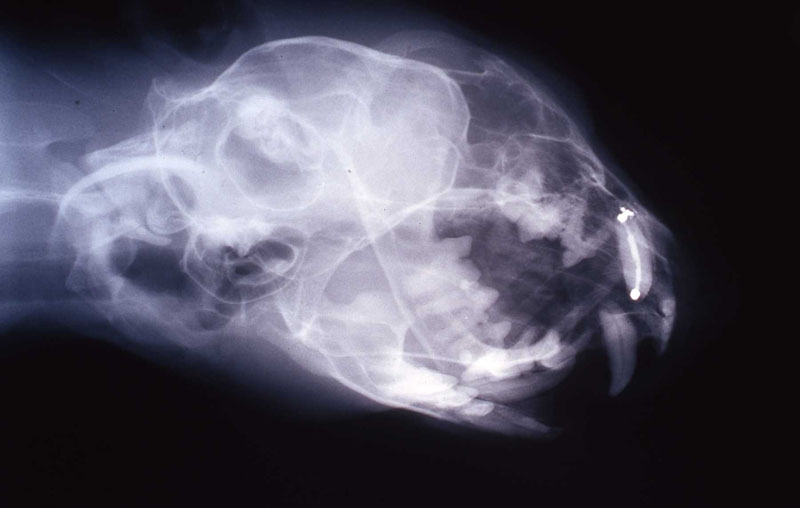

An 18 month old, 7.5 kg , female caracal (Caracal caracal caracal) new to the Milwaukee County zoo collection presented with a fractured right maxillary canine tooth during routine quarantine examination. The canine tooth had approximately 3 mm of its tip fractured off, the pulp chamber was exposed, and the tooth was darkened due to degeneration of of the pulpal tissue, and induction of food debris. There was no sign of an external drainage tract lesion. Radiographic examination revealed the presence of a periapical lesion 6mm by 7mm in diameter. The extra-oral surgical approach was chosen to debride the periapical lesion, resect the apex, and perform a retrograde fill in conjunction with the coronal or oblique endodontic fill.

The periapical lesion was debrided with small bone currettes. The exposed root apex was sectioned. Endodontic files were used to debride the entire root canal from the coronal end. Sodium hypochlorite and RC Prep (Root Canal Preparation©, Premier Dental Products, Co., 3600 Horizon Drive, King of Prussia, PA 19406-0974) was used to irrigate the canal during filing When the canal was prepared, irrigated, and dried, a PC pressure syringe (Pulpdent Corporation Pressure Syringe©, Pulpdent Corporation, 80 Oakland Street, Watertown, MA 02471, USA), was used to deposit the zinc oxide/eugenol paste until it extruded apically. Gutta percha points were fitted, placed and laterally condensed. A retentive preparation was made at the apical and coronal ends, and silver amalgam was used to seal the preparations. The surgical site was irrigated with sterile saline and closed with dissolving sutures.

lnteroperative and postoperative radiographs were obtained to verify endodontic working length and extent of endodontic fill.

The animal was reimmobilized using either a similar anesthetic regimen, or ketamine 6mg/kg and medetomidine (Domitor©, Pfizer Animal Health) 37 mcg/kg I.M., at 3 weeks, 14 months and 29 months. A small scar, approximately 1x4 mm, remains present at the incision site. Radiographs taken at each recheck showed healing of the periapical lesion, and normal bone repair in the surgical site.